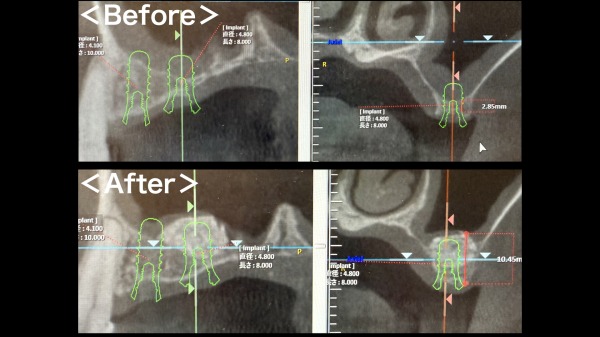

術前後のCT画像がこちらになります。3mm以下であった骨の厚みが10mm程度に増加しております。